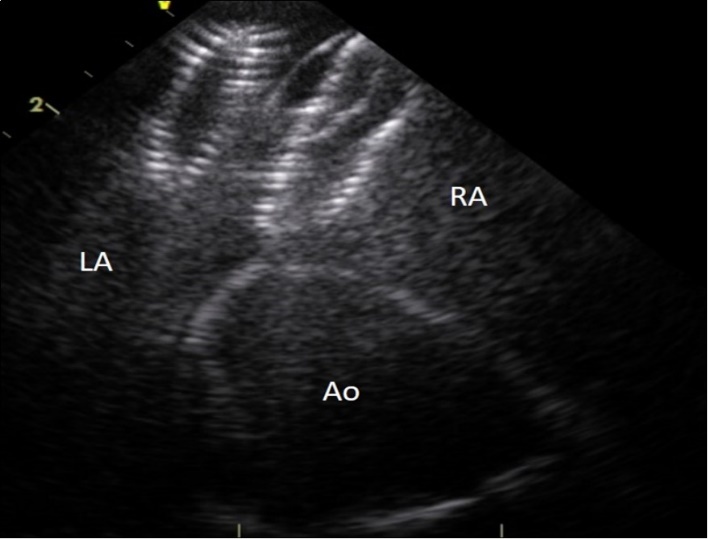

On examination, her heart rate was 71 beats per minute regular, blood pressure was 143/80 mm Hg, air saturation was 96% breathing ambient air and no fever. Jugular veins were not engorged. S1 and S2 were normal. There was a grade 3/6 ejection systolic murmur at right upper parasternal area. 24 hours ECG monitoring showed sinus rhythm. The neurological and pulmonary examination was normal. She underwent immediate transthoracic echocardiography and subcostal view showed a left-right shunt at the interatrial septum. Further evaluation revealed that the device embolized to the left ventricle and was lying in the left ventricular outflow tract with the distal extremity crossing the aortic ring. The device was displaced longitudinally with an important effect of stenosis. (Figure 1), (Figure 2). The entrapped device induced mechanical obstruction of the left ventricular outflow tract with a maximum/minimum gradients of 64/42 mmHg. The left ventricular function and size were normal. The mitral valve was normal with a minimal regurgitation. The right ventricle was mildly enlarged with normal function. The tricuspid valve function was normal. No pericardial effusion was detected. There was no gross thrombus deposition over the device in echography and no vegetation was detected anywhere.

Figure 2.Intracardiac ultrasound picture of the ASD Amplatzer device in place on the interatrial septum. RA :right atrium. LA:left atrium. Ao :aorta